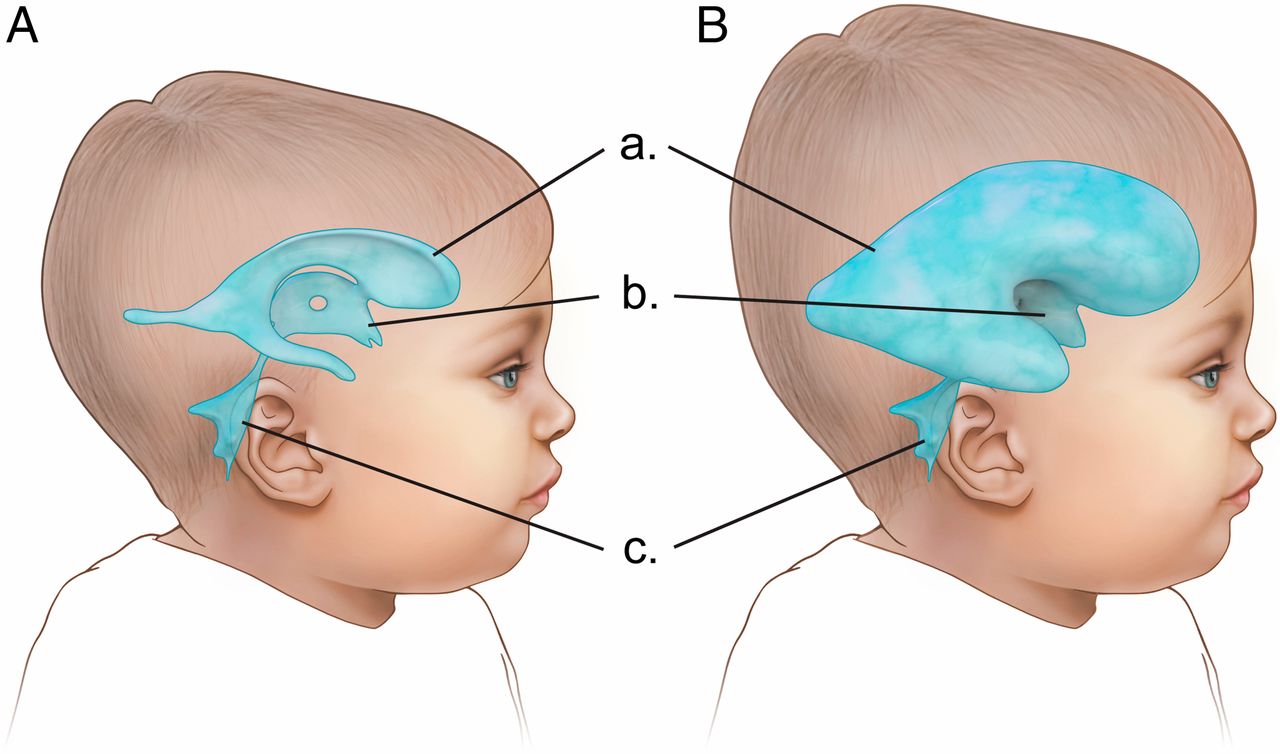

تصور کنید مغز به عنوان مرکز فرماندهی پیچیدهی بدن به دلایلی تحت فشار قرار بگیرد، فشاری که به صورت تدریجی و آرام اما بیوقفه اتفاق میافتد. در چنین شرایطی، مایع نخاعی در بطنهای مغزی جمع شده و وضعیتی به نام هیدروسفالی را ایجاد میکند. این اختلال، که در آن...